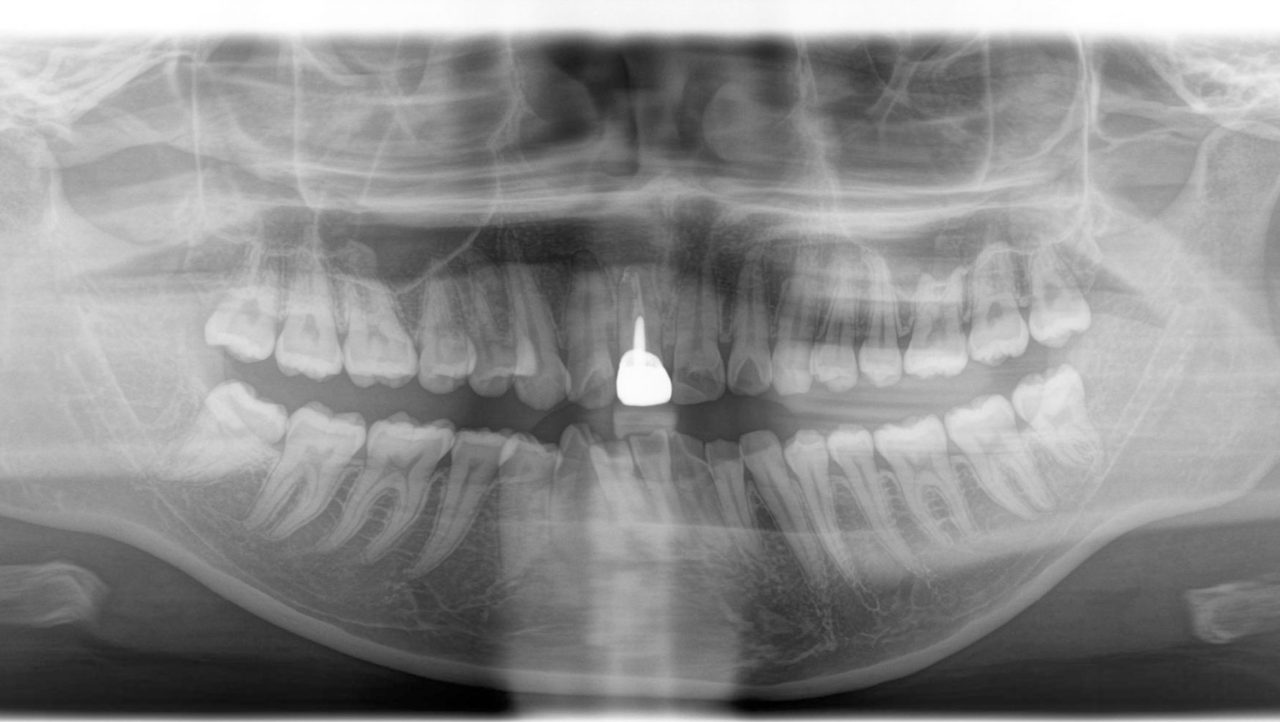

初診 2017.5.10

初診 パノラマレントゲン写真